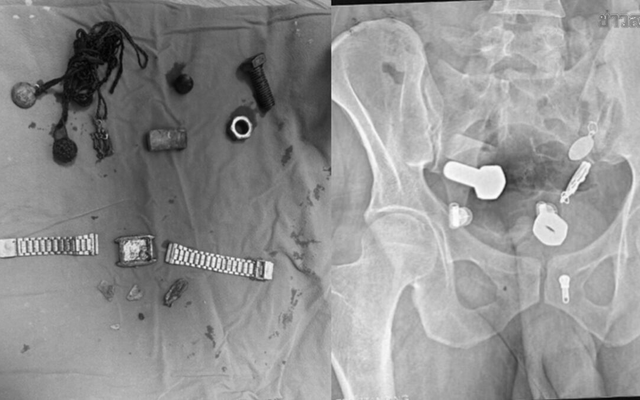

Các bác sĩ đã vô cùng kinh ngạc khi phát hiện một chiếc đồng hồ và vô số ốc vít trong bụng anh ta. Ca phẫu thuật kéo dài ba giờ.

Sau khi thăm khám và chụp X-quang, các bác sĩ thấy một chiếc đồng hồ đeo tay, bu lông và ốc vít, được gắn chặt vào nhau... trong bụng bệnh nhân.

Các bác sĩ đã cố gắng sử dụng ống nội soi để lấy vật thể ra nhưng không thành công, sau đó phải tiến hành một cuộc phẫu thuật lớn kéo dài hơn ba giờ để lấy toàn bộ dị vật ra khỏi cơ thể.

Theo Khaosod, đội ngũ y tế "sốc ngang" khi thấy nhiều vật thể, bao gồm cả một chiếc đồng hồ đeo tay trong bụng nam bệnh nhân. Sau phẫu thuật vài ngày tình hình sức khỏe bệnh nhân đang hồi phục tốt.